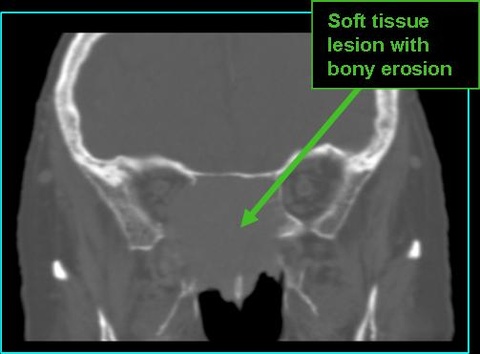

- On CT:

- Non-contrast: large, nodular mass with soft tissue densities; remodels and/or erodes bone